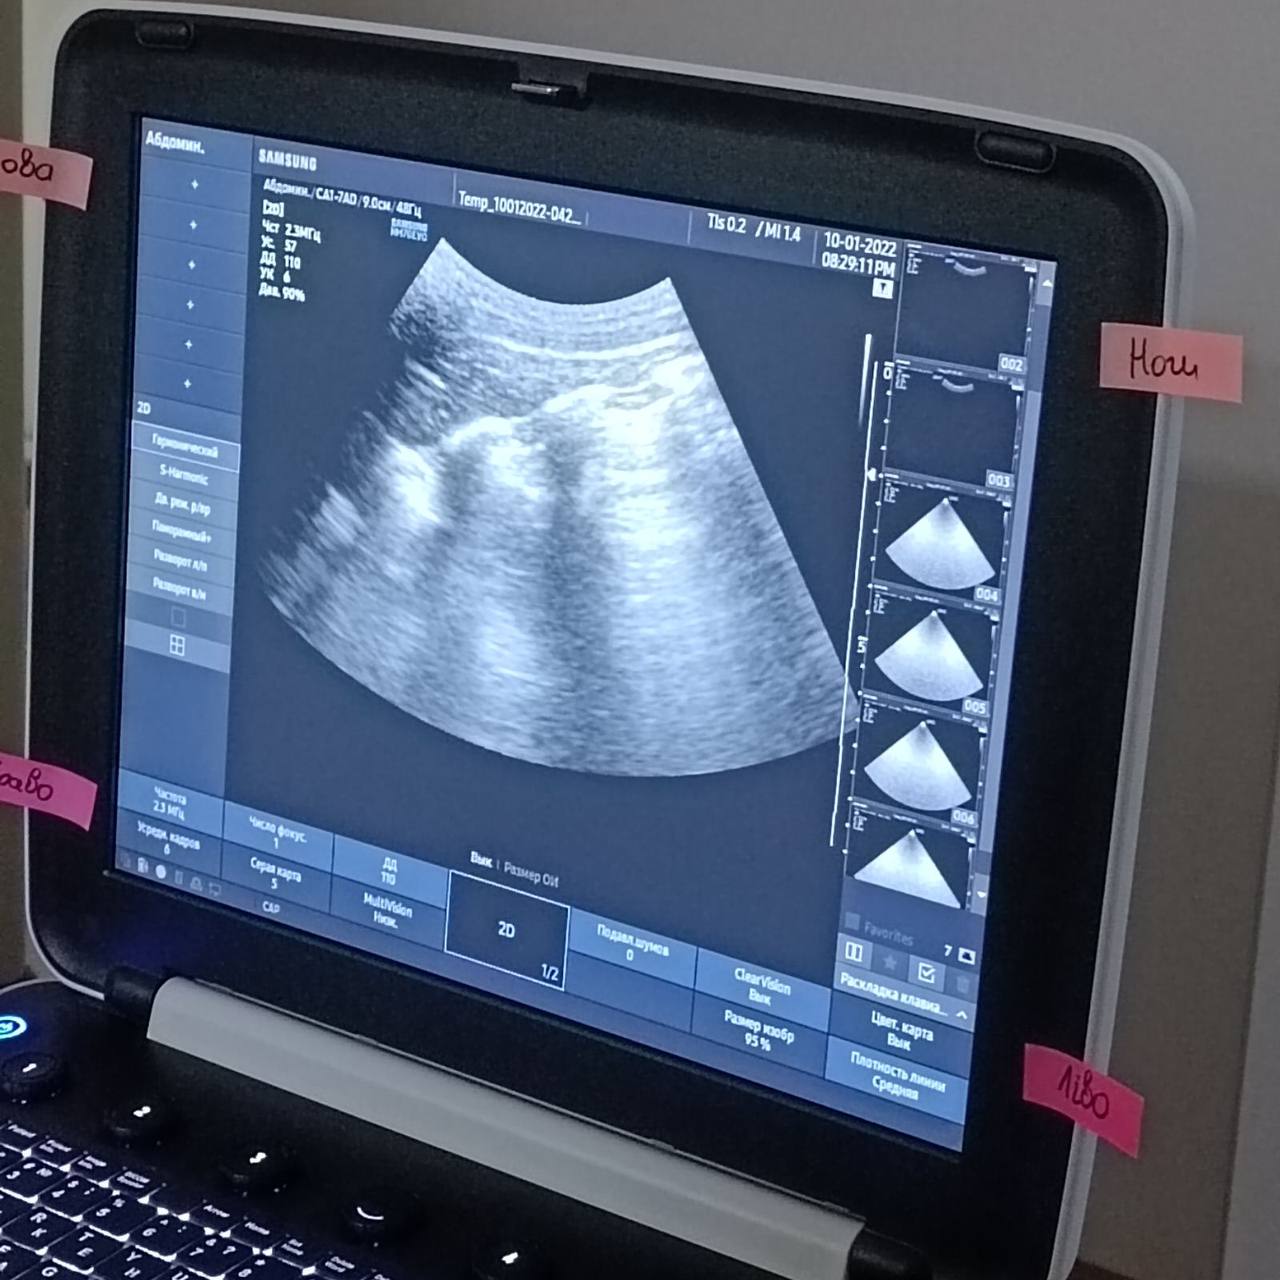

Учасники курсу відпрацювати з УЗД апаратами, правильно вибирати датчики, предналаштування, оптимізувати зображення, освоїли "алфавіт" з якого складається УЗД-легких, визначати основні показники УЗД-серця, необхідні при аналізі гемодинаміки, і звичайно ж пошук вільної рідини в черевній порожнині - FAST, e-FAST.

Основний акцент був направлений на практичні навички.

По закінченню слухачі самостійно могли провести УЗД-легких, вивести основні позиції при обстеженні серця, оволоділи протоколом FAST.